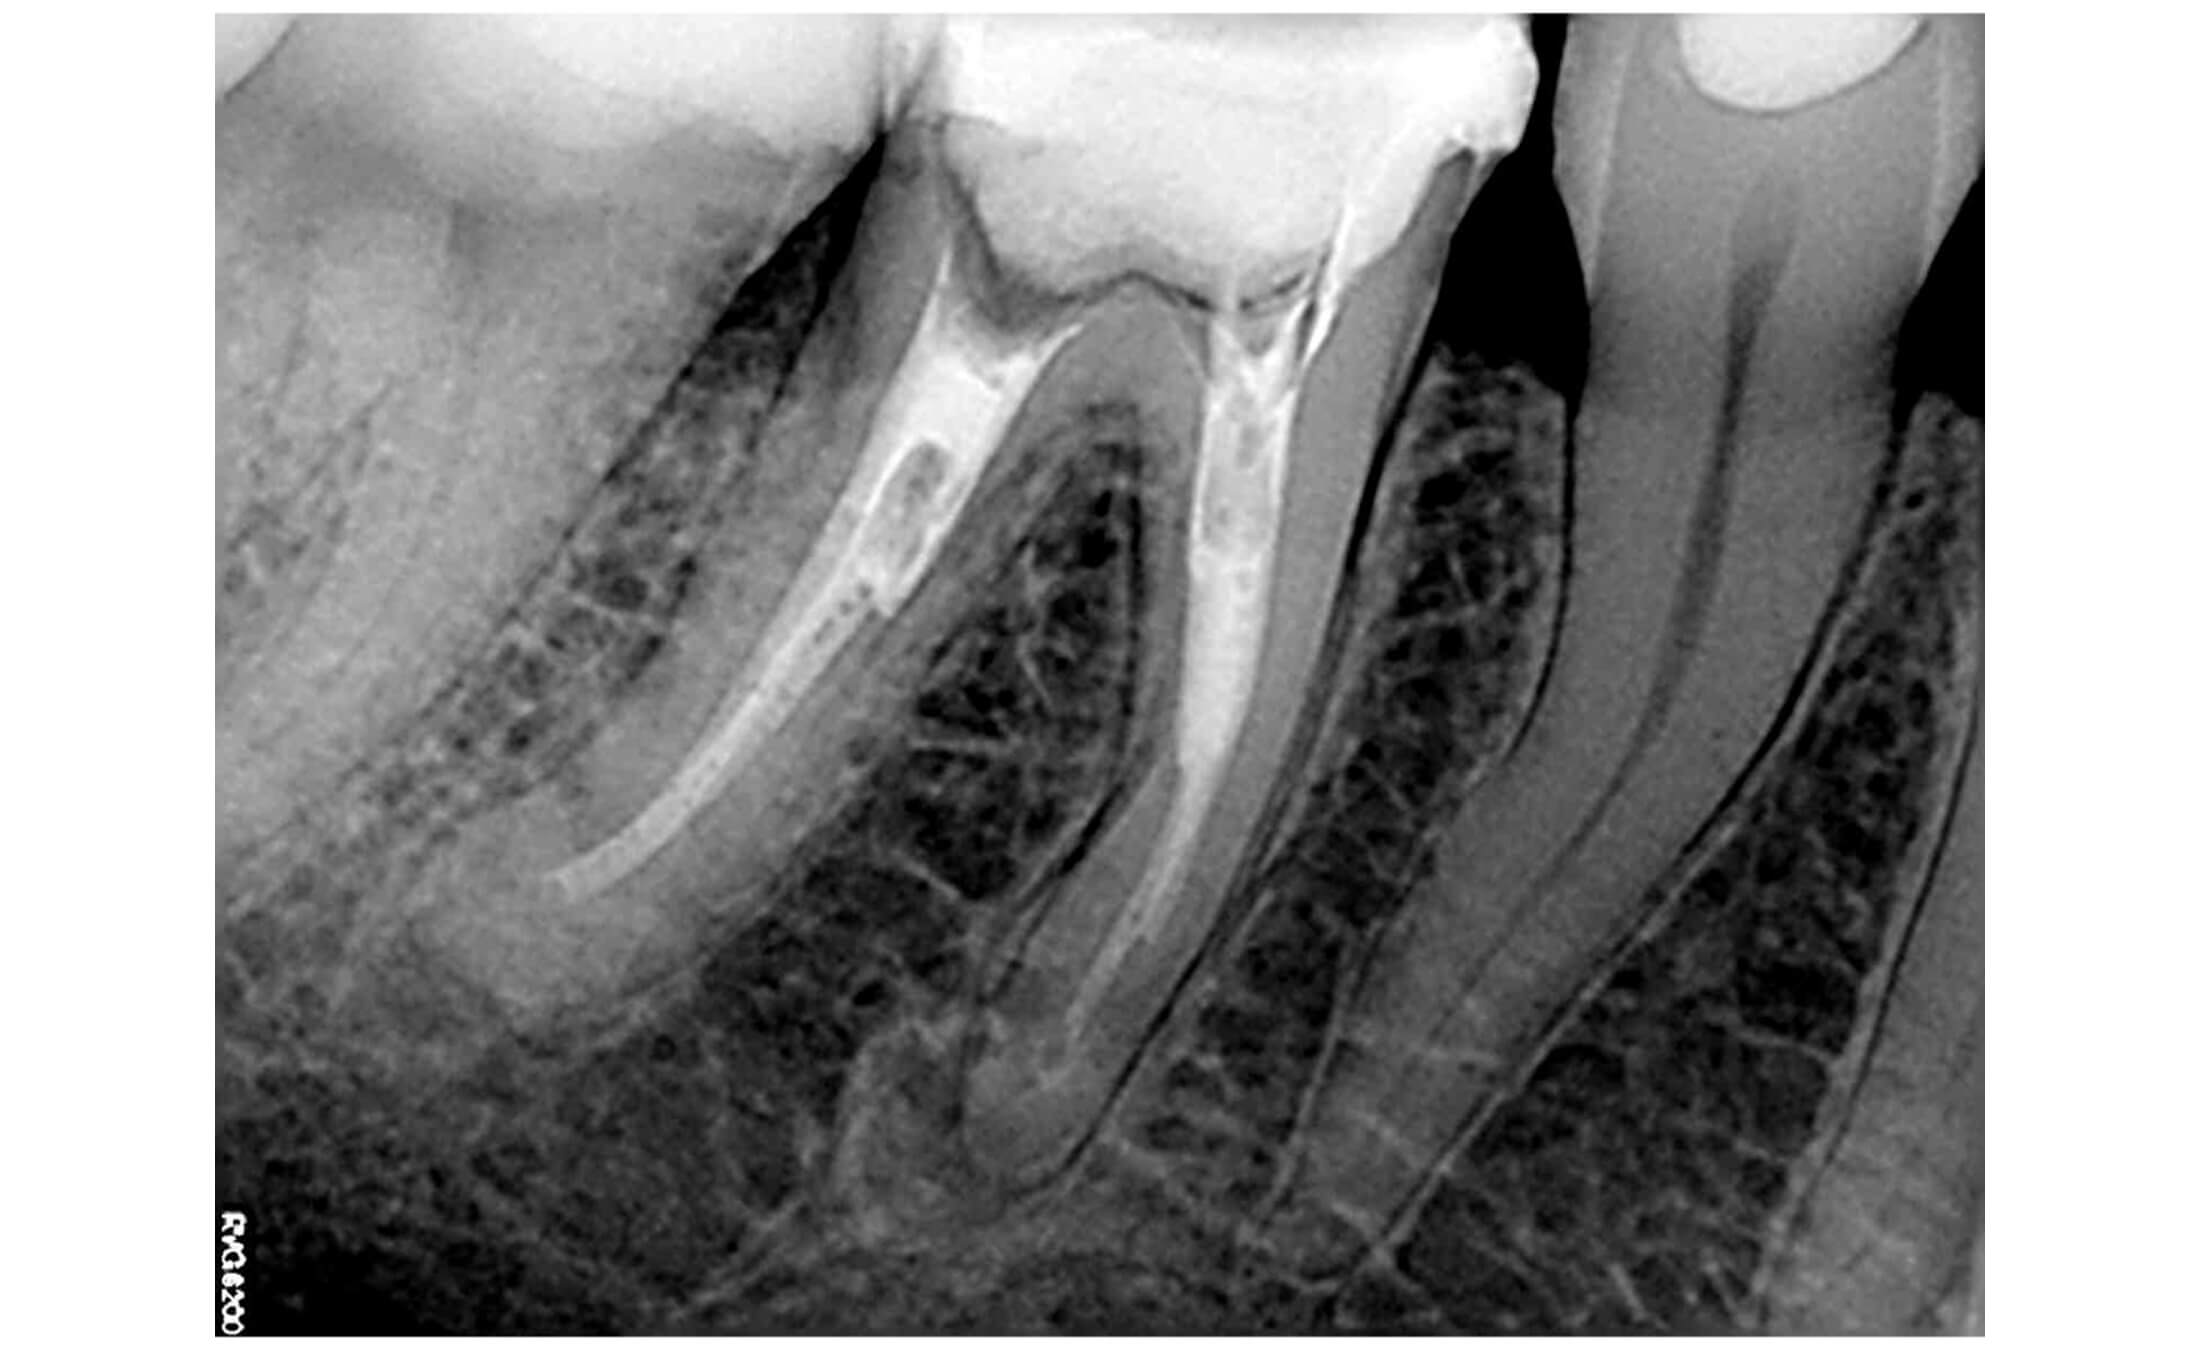

1. The patient presented with tooth #46 (lower right first molar) diagnosed with apical periodontitis, featuring two fractured endodontic instruments in the mesial root canals alongside overprepared canal orifices. Additionally, the distal root contained two misaligned fiber posts that had been cemented non-axially within the canal space, further complicating the endodontic retreatment. (Image 1,2,3)